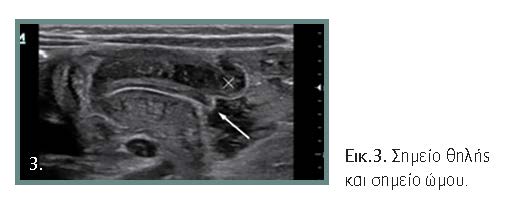

Η διάγνωση τις περισσότερες φορές είναι προφανής, όμως υπάρχουν άτυπες μορφές που μπορεί να προβληματίσουν τον κλινικό ιατρό (εικόνες 1, 2, 3, 4). Αλυσιδωτές επιπτώσεις στον οργανισμό συνθέτουν την κλινική εικόνα και τις επιπλοκές της νόσου. Με την εξέλιξη της κλινικής εικόνας και όσο δεν αντιμετωπίζεται η απόφραξη, μπορεί να εμφανιστούν βαρύτατες οξεοβασικές και ηλεκτρολυτικές διαταραχές. Οι διεγχειρητικές επιπλοκές πρέπει να αναγνωρίζονται και να αντιμετωπίζονται αμέσως γιατί οι επιπτώσεις είναι μοιραίες.